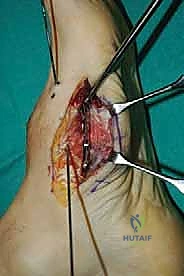

2. الشق الجراحي والوصول للمفاصل

يتم عمل شق جراحي واحد أو شقين (أحدهما في الجزء العلوي الداخلي والآخر في الجزء الخارجي) للوصول إلى مفاصل منتصف القدم دون الإضرار بالأوتار الحيوية والأعصاب والأوعية الدموية. يتم استخدام تقنيات الجراحة الدقيقة (Microsurgery) للحفاظ على الأنسجة المحيطة السليمة.

3. إزالة الغضاريف التالفة (Joint Preparation)

هذه هي الخطوة الأهم. يقوم الجراح بكحت وإزالة جميع الغضاريف المريضة والتالفة من بين العظام المراد دمجها. يجب الوصول إلى العظم الإسفنجي الصحي (Cancellous bone) الذي ينزف دماً، لأن هذا الدم يحتوي على الخلايا الجذعية وعوامل النمو الضرورية لعملية الالتحام (Fusion).